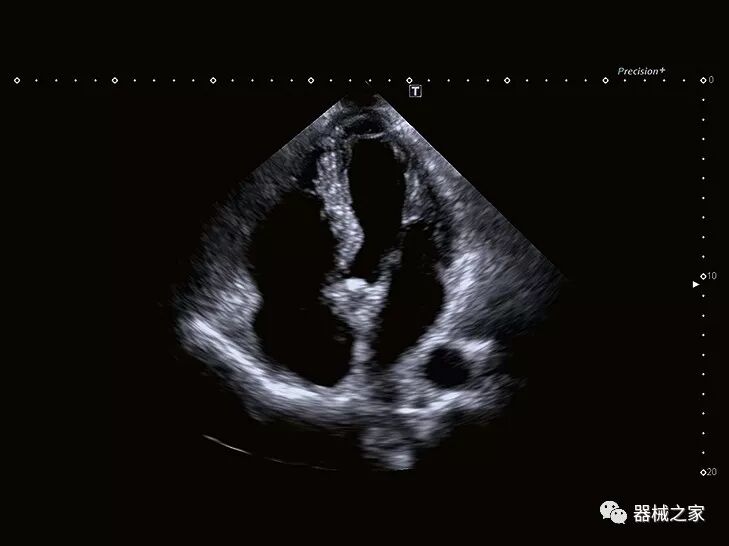

供应商已经超越了基本的二维和三维成像,提供了重建图像的新方法,以加快评估速度并使其更易于理解。

在几年前,超声波无法对小型慢流血管中的血流进行成像,但现在有少数供应商提供具有此功能的系统。该特征提供了另外一种检查病变以指示癌症或炎症的方法。其中一个是佳能Aplio 900 CV系统,它可以显示毛细血管中的血流量。日立的Arietta 65中程系统提供了一种可视化小血管的功能,可以更好地观察肾脏等器官的灌注情况。三星RS85还提供MV-Flow可视化慢流微血管结构。

Baptist Health South Florida成为去年秋天西门子医疗保健公司Acuson Sequoia的首个商业安装网站。该系统将有助于增强胃肠病学,初级保健和减肥专业的成像能力。Sequoia可实现高分辨率成像,自动适应患者的体型和个人身体特征,有助于更加自信的诊断。它适应患者的组织密度,刚度和超声波束吸收的生物声学变化。这使得系统可以穿透高达40厘米而不会因衰减回波信号而导致图像质量下降。